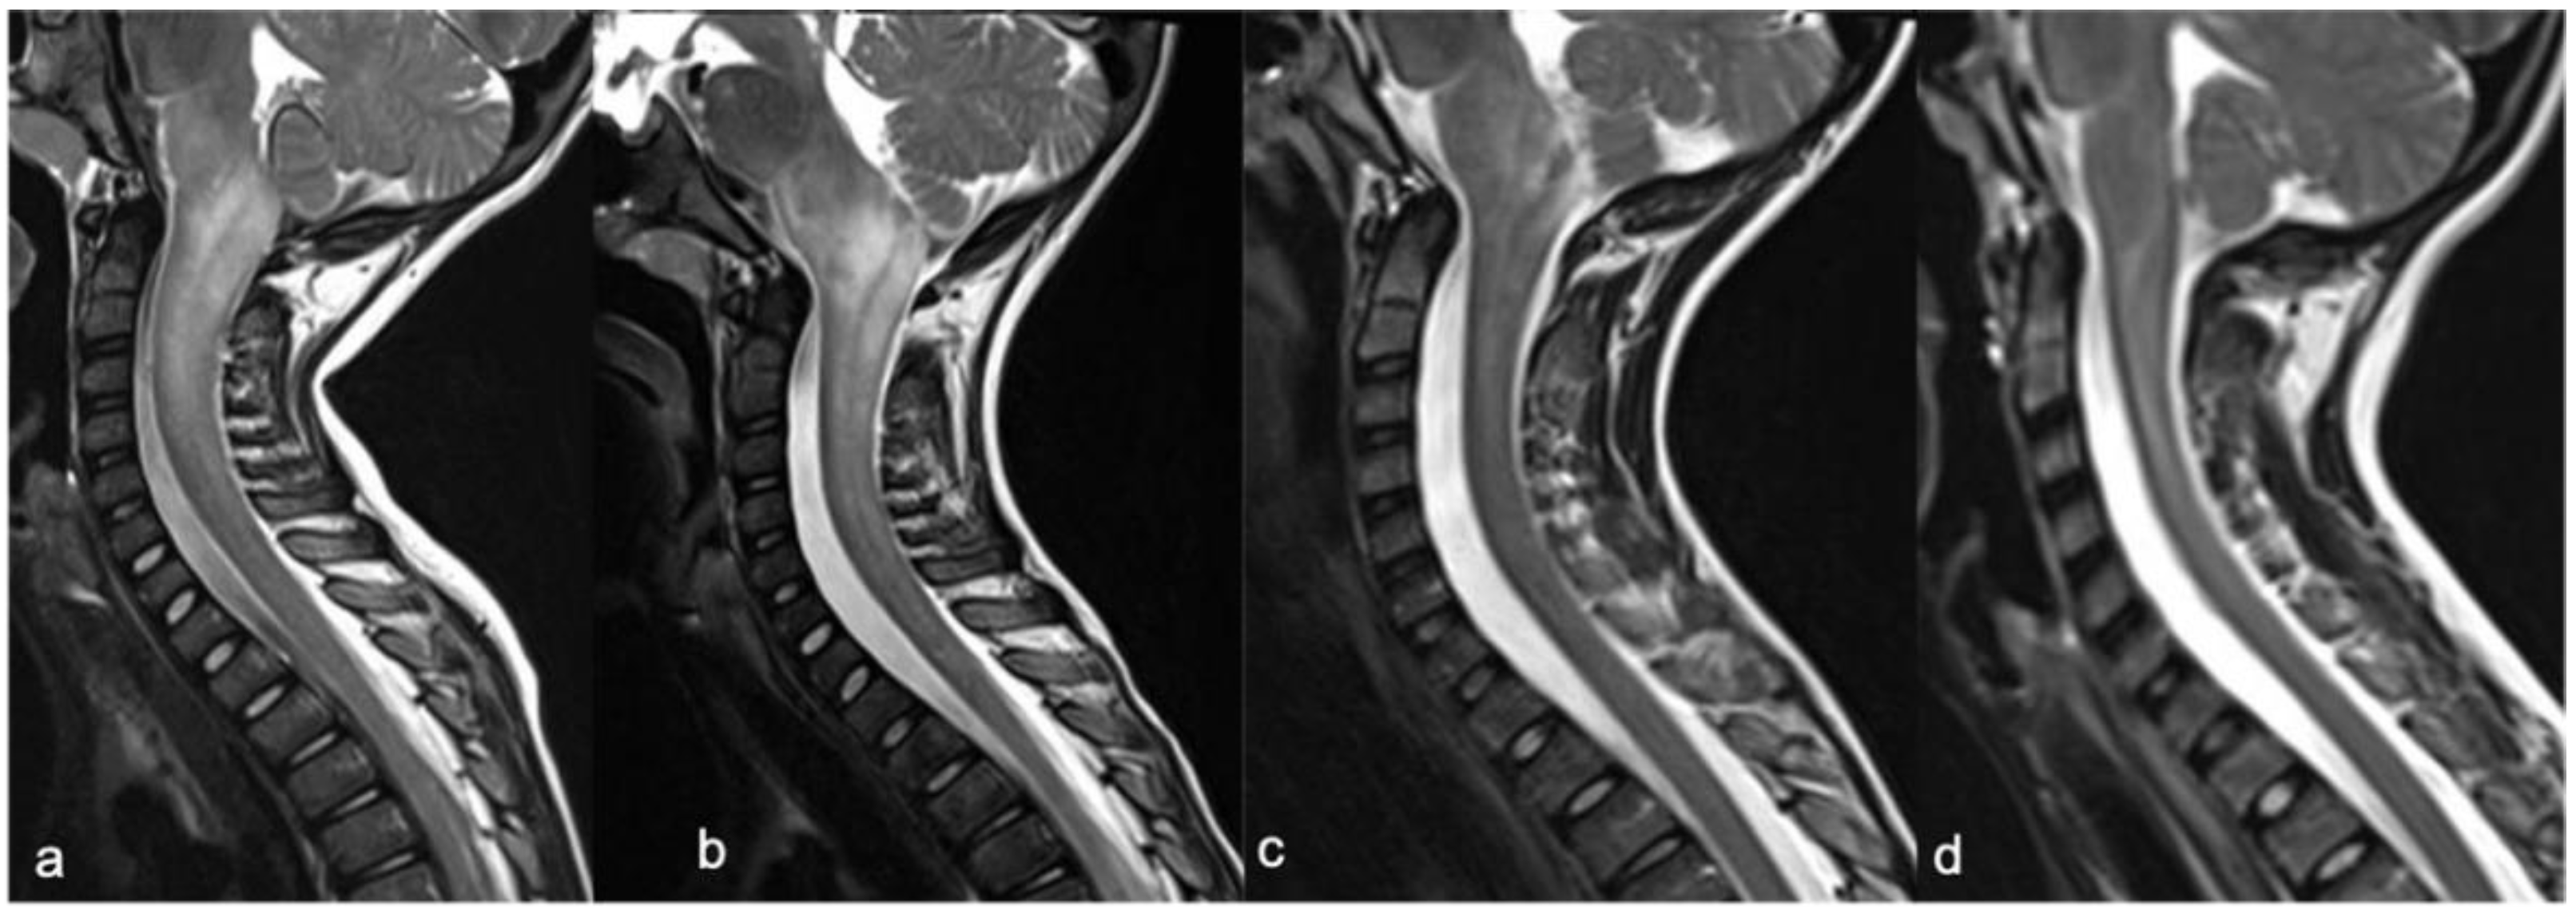

2. Gliomas and Mixed Neuronal–Glial Tumors

2.1. Gliomas